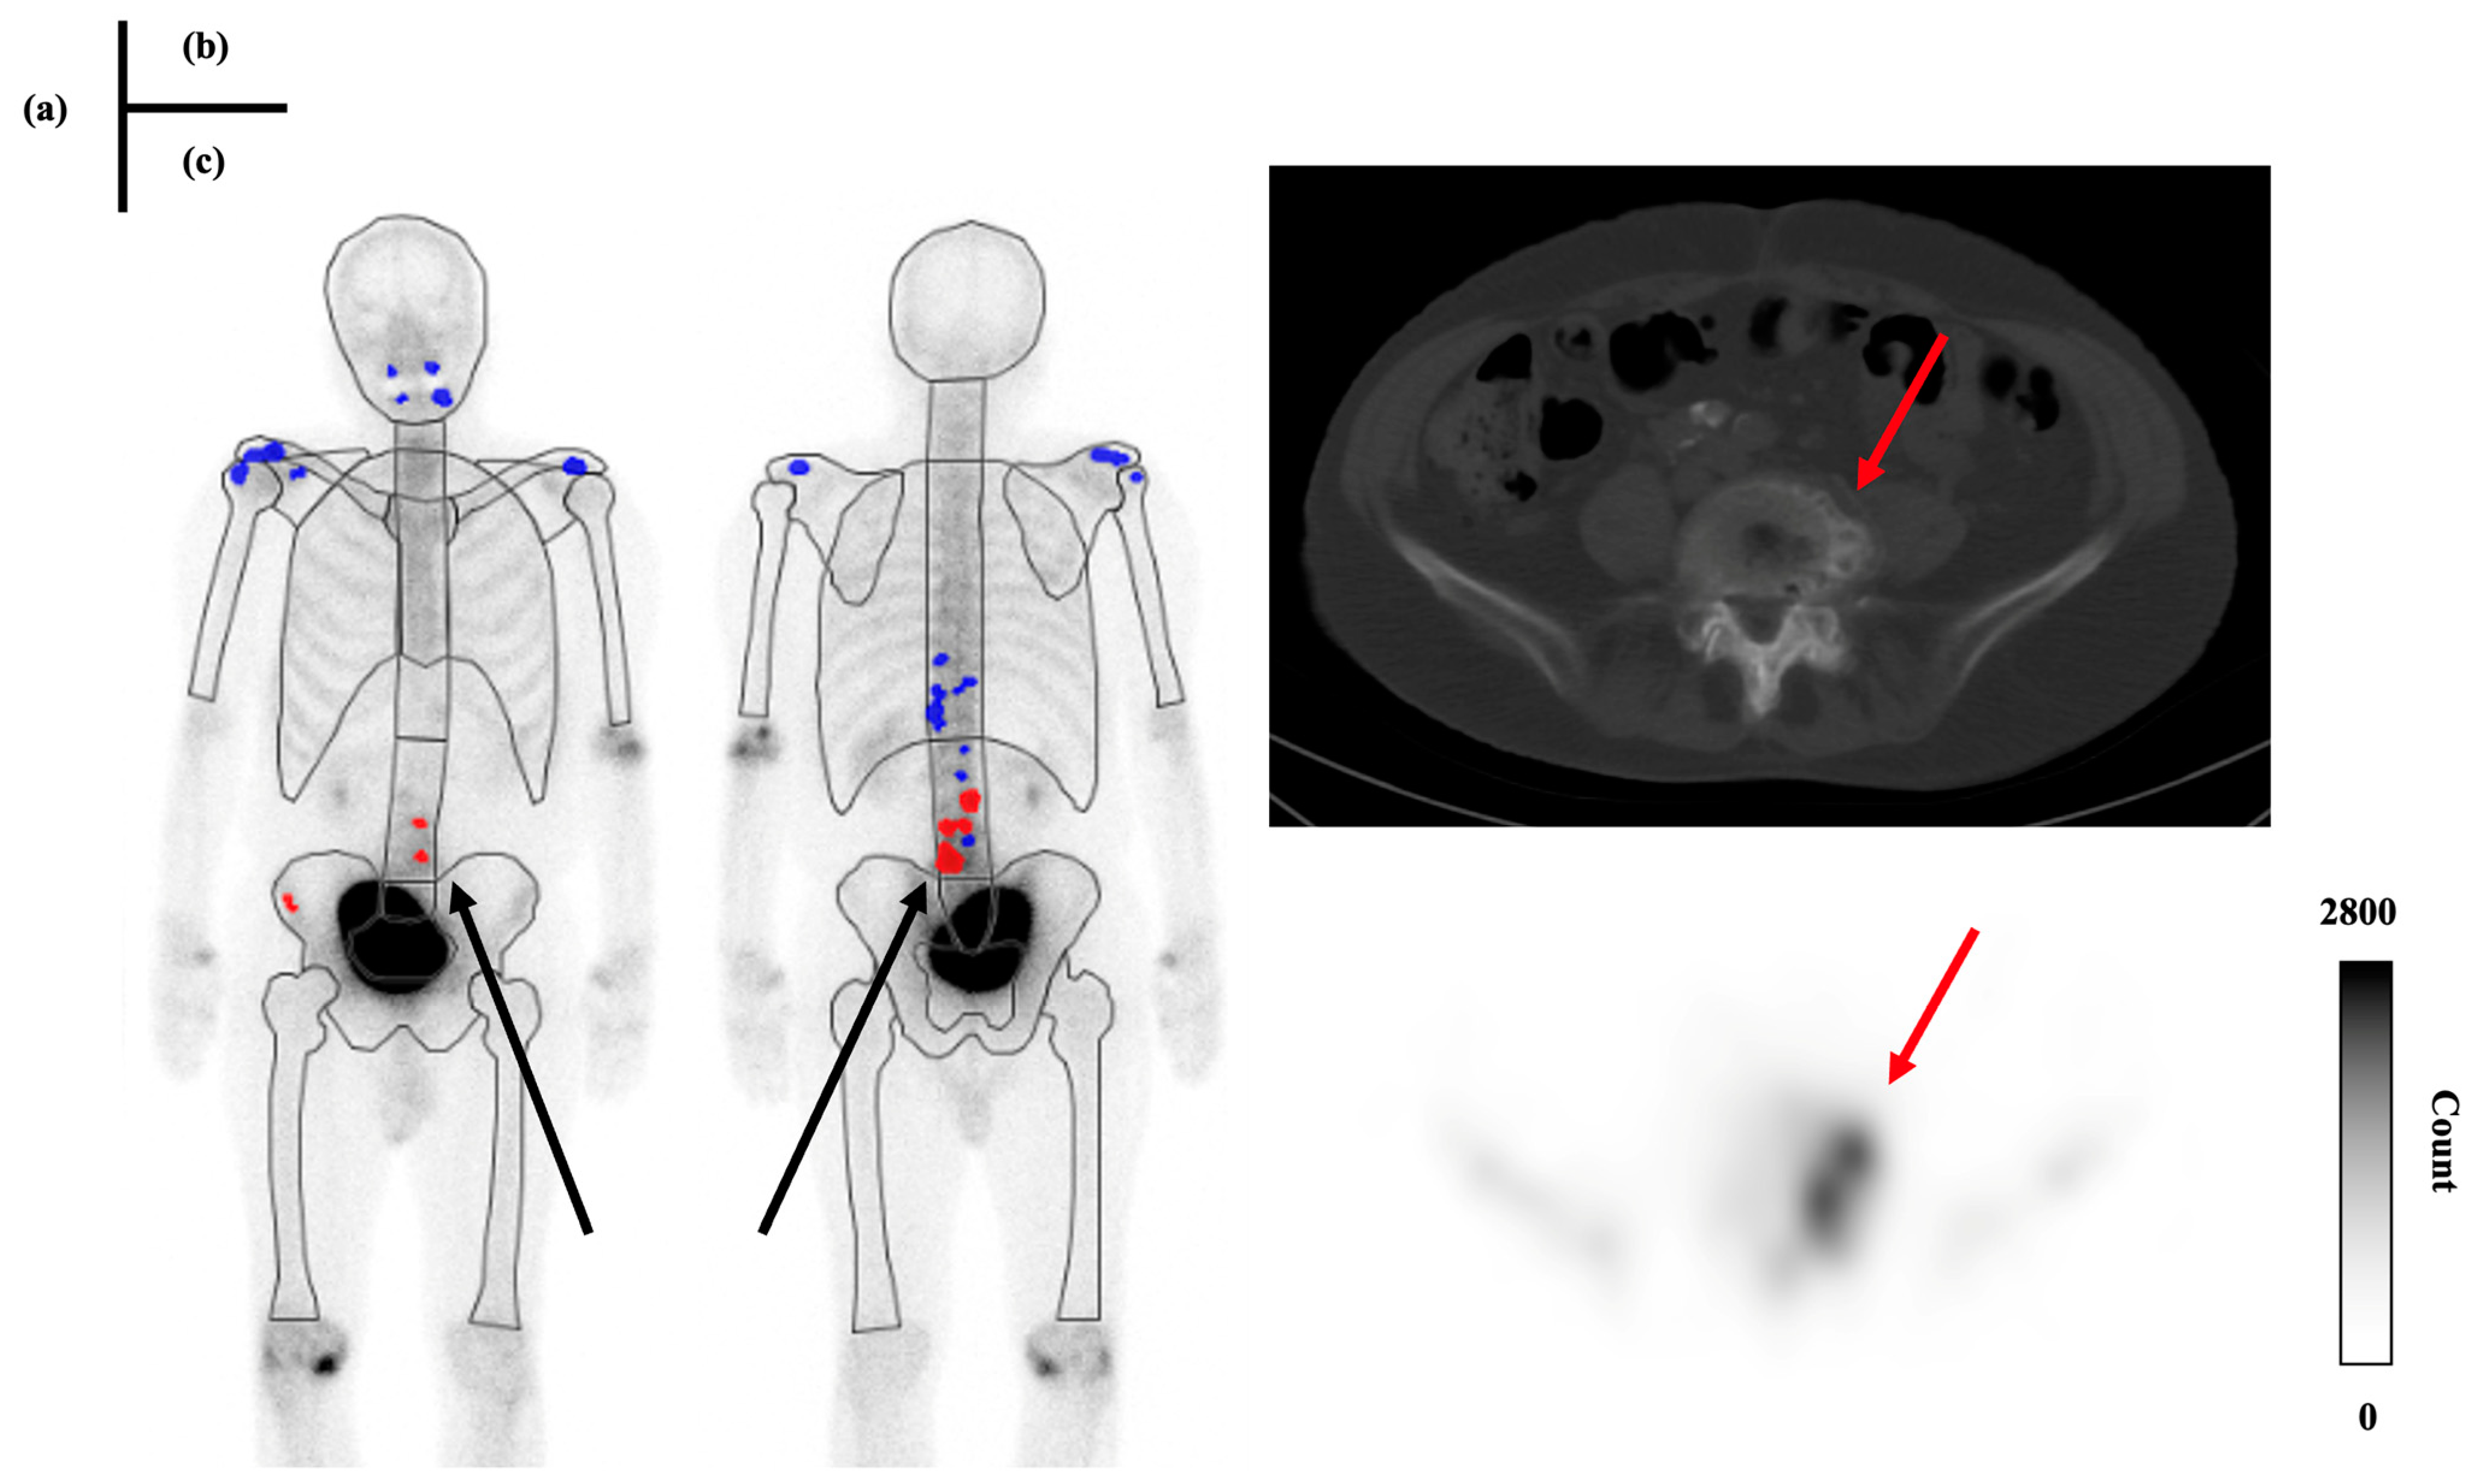

2.3. Imaging

2.4. Criteria for the Presence or Absence of Bone Metastasis

2.5. Case Grouping and Data Analysis